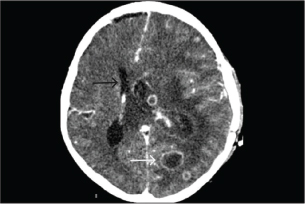

One-week post-VAV-ECMO, while still on corticosteroids for 15 days, the patient developed a new high-grade fever that persisted for 9 days. On day 23 of admission, he complained of progressive headache and agitation. Neurological examination revealed bilaterally dilated (5 mm) but reactive pupils without focal deficits. Emergency contrast-enhanced computed tomography (CT) of the brain demonstrated multiple cerebral abscesses with vasogenic edema and one lesion located at the left periventricular area, adjacent to the lateral ventricle (Fig. 1). In immunocompetent individuals, the most common pathogens were Streptococcus spp., Staphylococcus aureus, Enterobacteriaceae, Pseudomonas aeruginosa, and anaerobes. In immunocompromised hosts, it is most commonly caused by toxoplasmosis, Nocardia spp., Candida spp., Aspergillus spp., and Cryptococcus spp. Empirical antimicrobial therapy was adjusted to intravenous meropenem and vancomycin to provide coverage for multidrug-resistant bacteria and methicillin-resistant Staphylococcus aureus (MRSA). A right frontal craniotomy was subsequently performed for abscess drainage and diagnostic confirmation, along with placement of an external ventricular drain (EVD) in the left lateral ventricle for cerebrospinal fluid (CSF) sampling and intracranial pressure control.

Fig. 1. A computed tomography scan of the brain with contrast on day 23 of admission showed two ring-enhancing lesions located in the left occipital lobe (black arrow) and left periventricular region, adjacent to the lateral ventricle (white arrow).